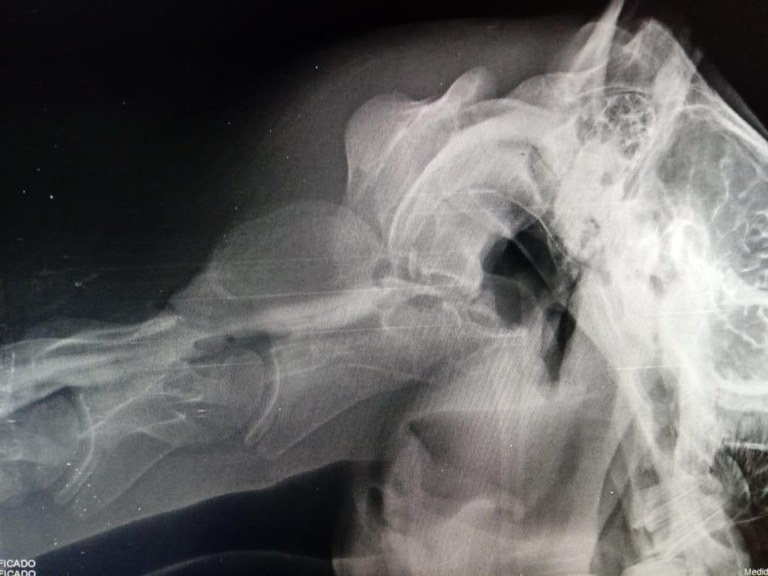

Equipe realiza procedimento inédito no Hospital Veterinário

Mielografia é realizada pela primeira vez no Hospital Veterinário/CCA